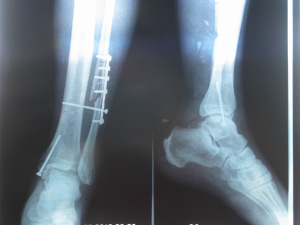

Перелом малоберцовой кости, как и другие переломы, начинает лечиться с восстановления прежнего положения костной части, в которой она находилась до травмы. Если травма не сопровождалась смещением, обычно накладывают гипсовую повязку сроком от четырех до шести недель. Гипс может накладываться до центра голени, все зависит от места повреждения. До середины бедра гипс накладывается при переломах головок малоберцовых костей или их шеек.

Если части сломанной кости изменили положение относительно друг друга, то есть произошло смещение, лечение усложняется. Важно произвести репозицию таким образом, чтобы части кости остались в нужном положении. Если этого не получилось сделать вручную, применяется скелетное вытяжение. Его суть состоит в просверливании отверстия в кости, к которой прикреплена малая берцовая кость. В это отверстие вставляется металлическая спица, к ней подвешивается груз. Благодаря грузу пяточная кость тянется вниз, а фрагменты сломанной кости постепенно принимают нормальное положение.

При неэффективности скелетного вытяжения приходится выполнять оперативное вмешательство, в процессе которого костные части удерживаются с помощью винтов, штифтов и пластинок.

После того как малая берцовая кость срослась, эти элементы удаляются. Так как иногда происходит повреждение нервов, необходимо прибегать к дополнительным мерам.